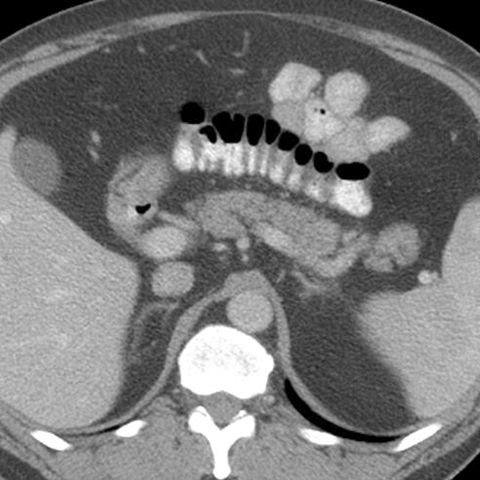

Normal Pancreas, Axial CT [1 of 5]